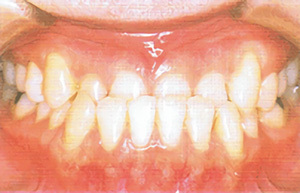

type02

• 口を閉じると、下の歯列が上の歯列よりも前に出ている

• 顎がしゃくれている

• 下顎が発達しすぎている

• うまく咀嚼できない

• 言葉が聞き取りにくい、と言われることがある

「反対咬合(はんたいこうごう)」である可能性があります。一般的には「受け口」と言われます。遺伝的な要因もありますが、上唇を噛んだり、舌を突き出す等の癖が原因になっていることがあります。